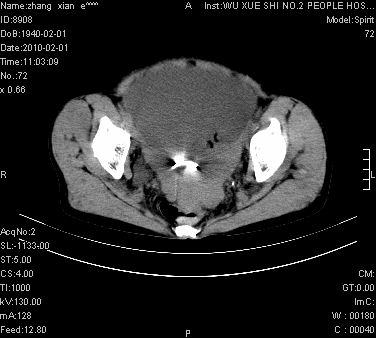

标题: CT24434:70岁 女 腹胀,腹水原因待查 [打印本页]

标题: CT24434:70岁 女 腹胀,腹水原因待查

大量腹水,脾脏囊性占位,子宫颈占位,右侧腹股沟淋巴结肿大,建议+c,先查妇科。

腹盆腔大量积液,子宫增大,子宫颈增大外形不规则,内见低密度影,膀胱后壁显示不清,右腹股沟肿大淋巴结,脾脏囊性占位,子宫颈占位,子宫颈癌?建议增强。

腹盆腔大量积液,子宫增大,子宫颈增大外形不规则,内见低密度影,膀胱后壁显示不清,右腹股沟肿大淋巴结,脾脏囊性占位,子宫颈占位,子宫颈癌?建议增强。支持!